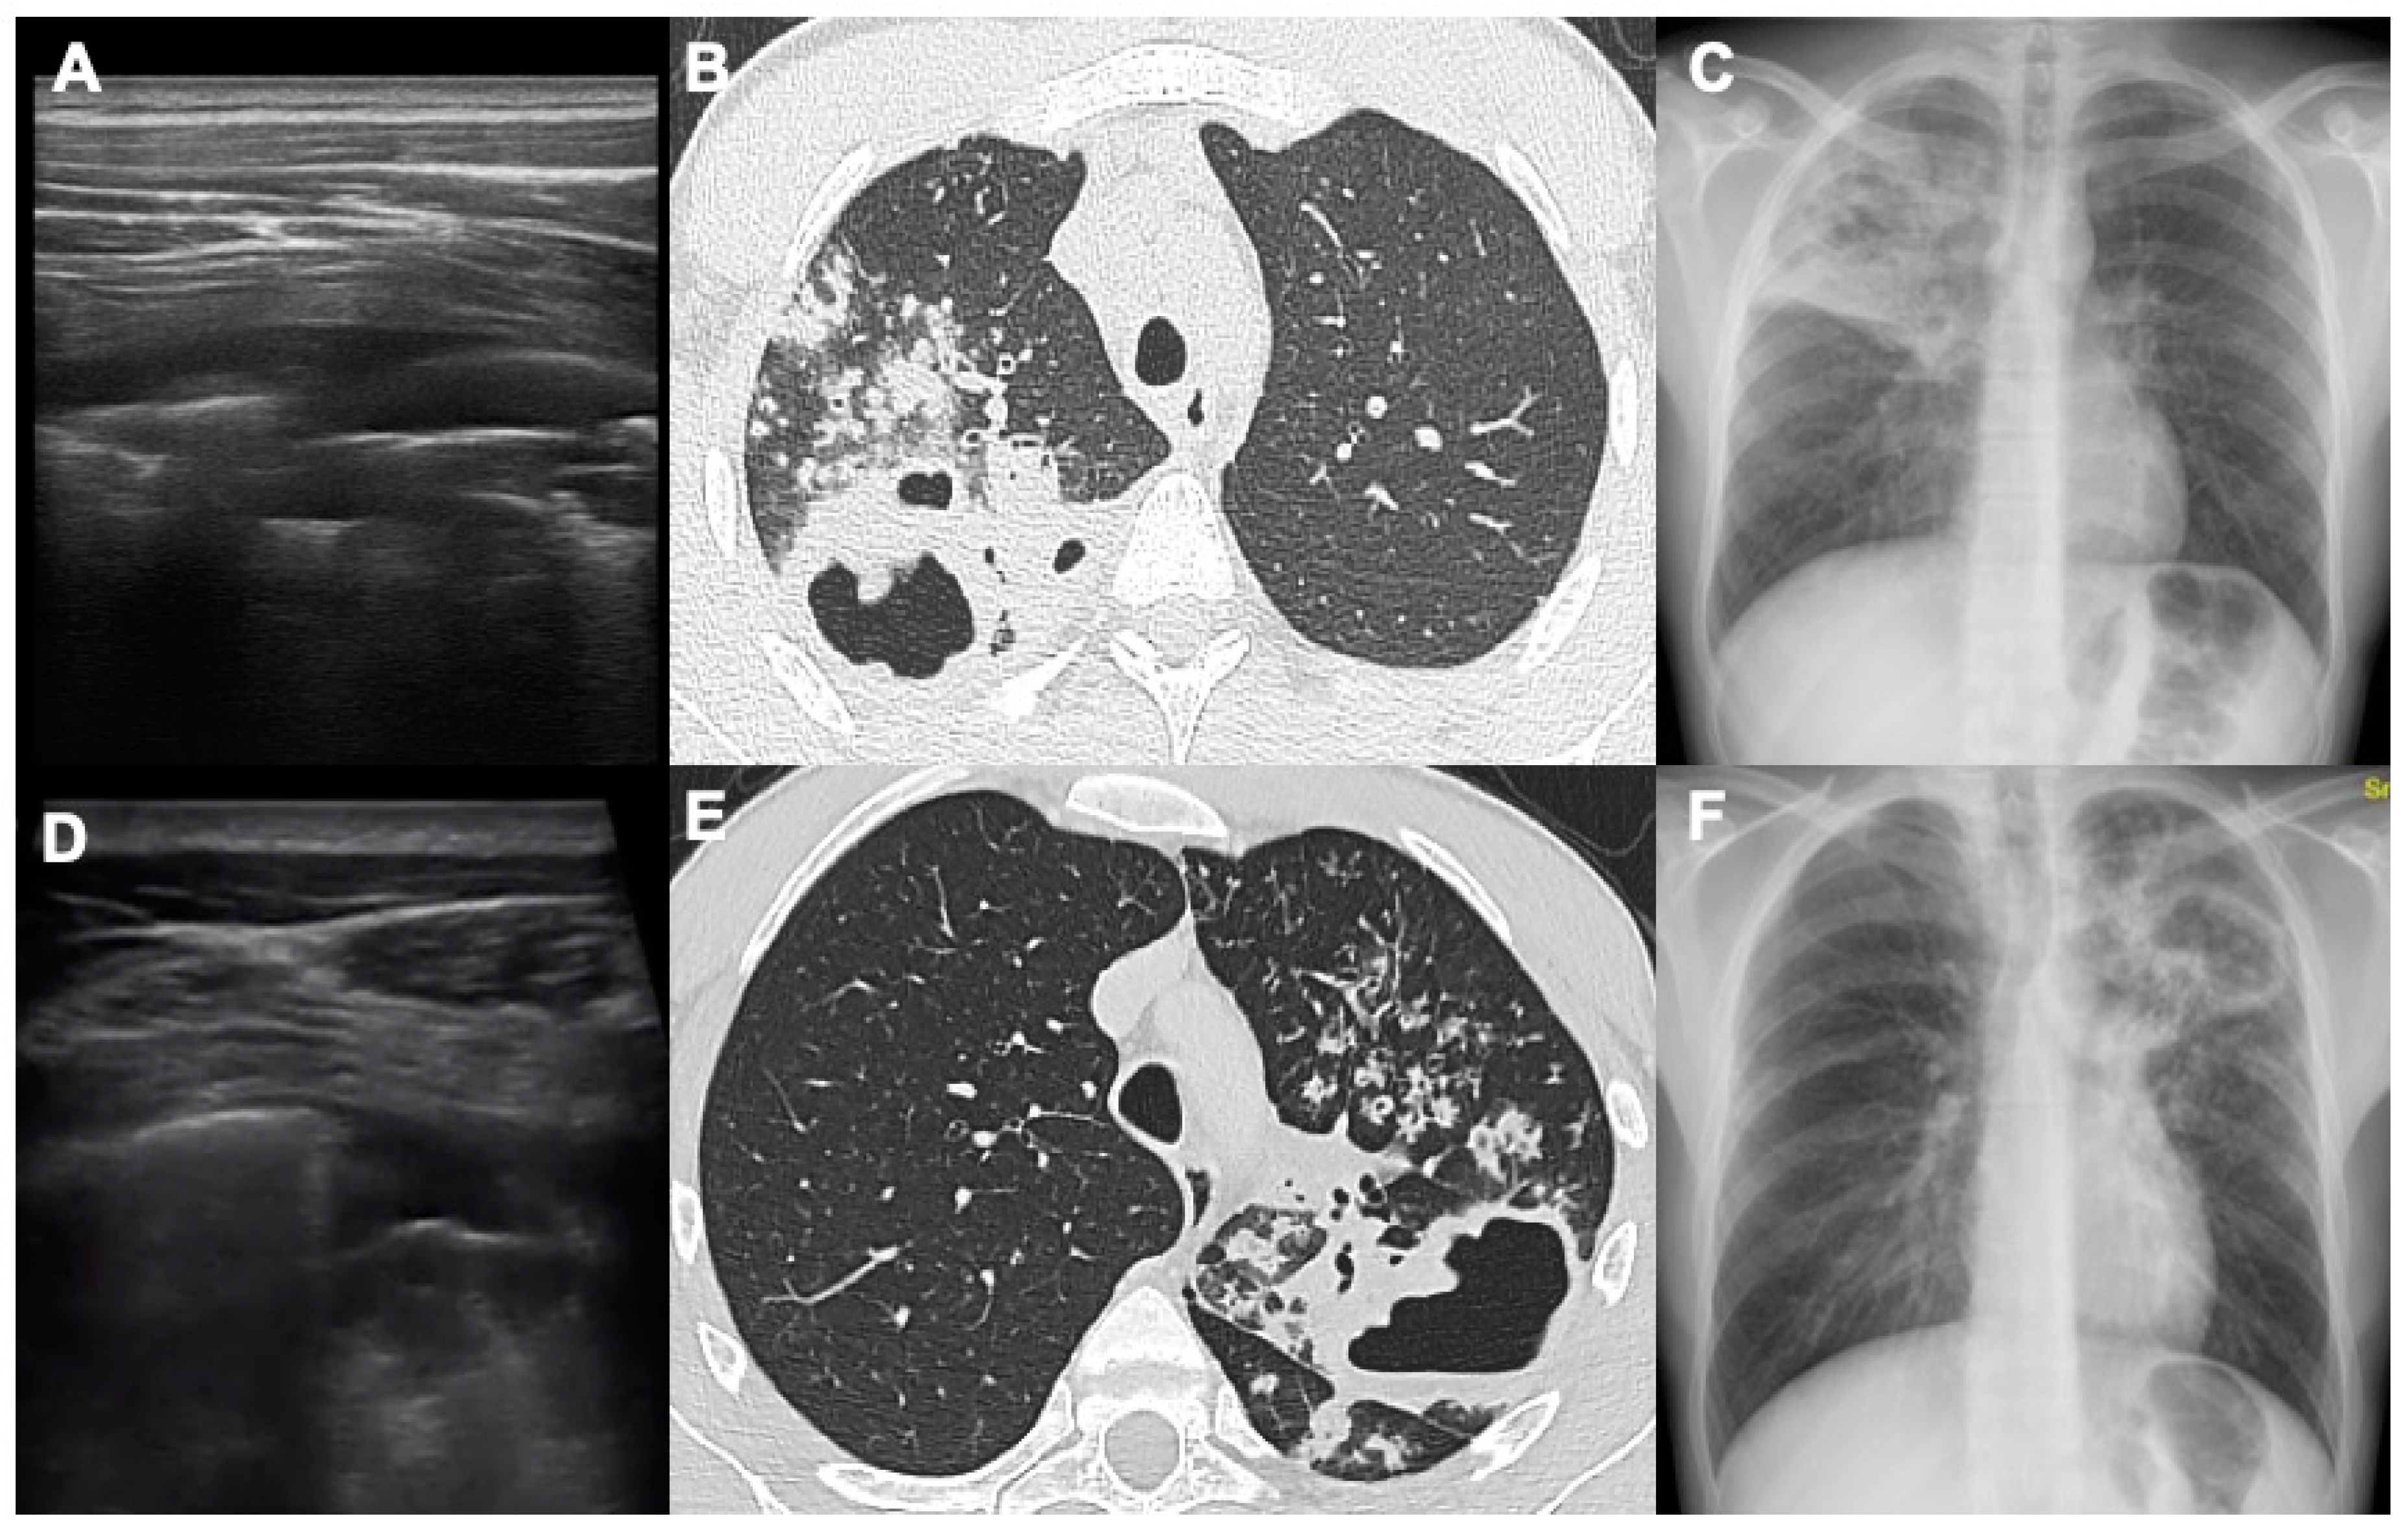

- Giannelli F, Cozzi D, Cavigli E et al. Lung ultrasound (LUS) in pulmonary tuberculosis: correlation with chest CT and X-ray findings. J Ultrasound 2022, 25(3):625-634. [CrossRef]

- Montuori M, Casella F, Casazza G et al. Lung ultrasonography in pulmonary tuberculosis: a pilot study on diagnostic accuracy in a high-risk population. Eur J Intern Med 2019 66:29–34. [CrossRef]